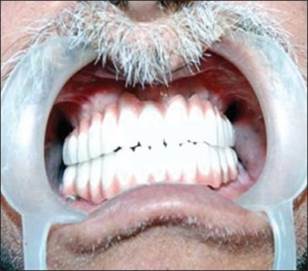

Un paciente de sexo masculino de 58 años había acudido al ala de pacientes externos de nuestro departamento, con una queja principal de falta de diente en los arcos maxilar y mandibular. El paciente quiere tener una prótesis fija ya que no estaba contento con la dentadura convencional [Figura 1] y [Figura 2] . Se registró un historial de casos adecuado para el paciente, incluido un historial médico que no era contributivo, con pruebas de laboratorio relevantes, exámenes dentales y orales. Se prepararon impresiones de diagnóstico y moldes. Se realizó un examen exhaustivo y el paciente estaba motivado para implantar prótesis. El mapeo óseo se realizó para evaluar el ancho del hueso, mediante el uso de ortopantamografía (OPG), se calculó la longitud del hueso disponible y se seleccionaron los implantes de tamaño apropiado [Figura 3]. Se preparó una plantilla quirúrgica para el maxilar y la mandíbula, y la posición de los implantes se decidió antes de la cirugía colocando un taladro en el implante.

Figura 1: Fotografía preoperatoria maxilar |